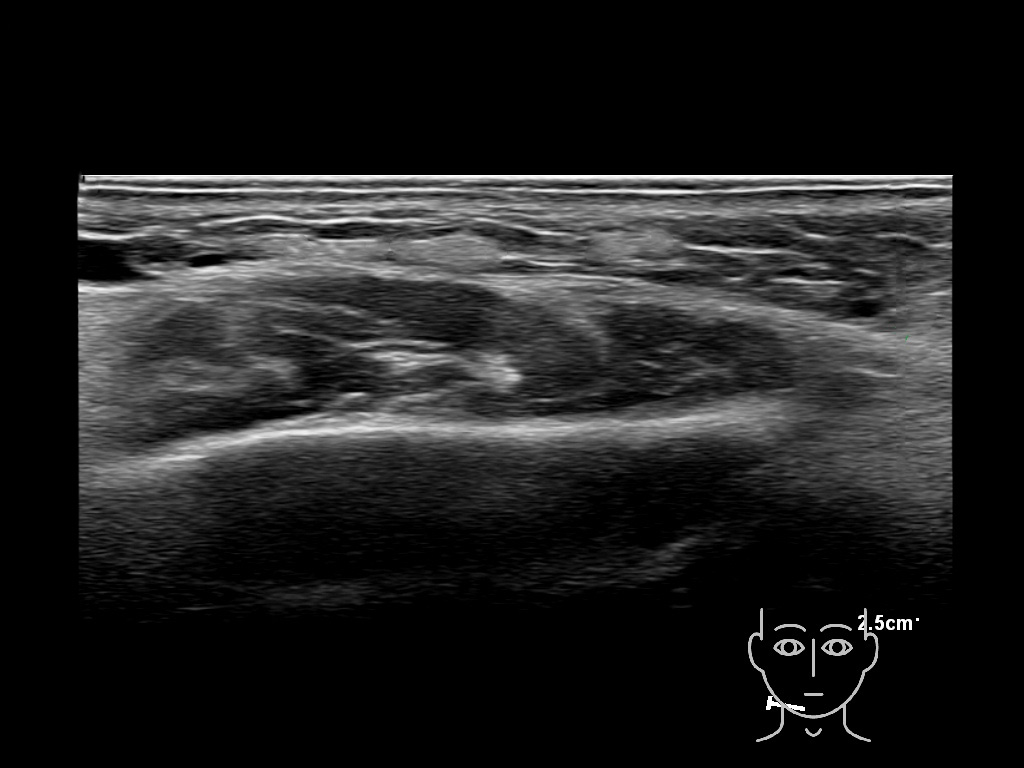

Draw in the image on the right where the fillers are located. To check if your answer is correct, please click on the secondary image.

Draw in the second image below where the fillers are located. To check if your answer is correct, swipe the first image to the right.